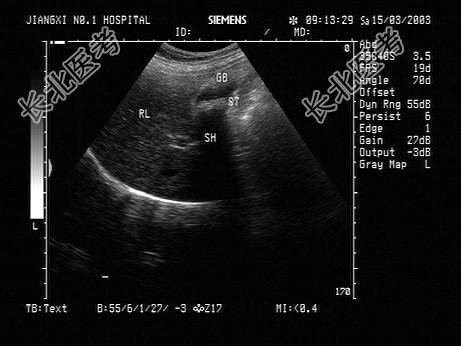

- 单项选择题女性患者,42岁, 反复上腹疼痛不适多年,加重3天。声像图如图所示, 最可能的诊断为 ( )

A、胆囊癌

B、胆囊泥沙样结石

C、胆囊息肉

D、胆汁淤积

E、胆囊蛔虫